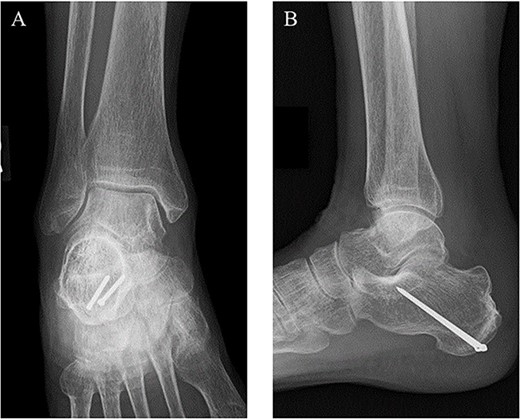

The surgery was performed under general anesthesia in the prone position with an air tourniquet and a fluoroscopy. First, an ~6 cm straight incision on the skin just above the calcaneal tuberosity was placed, and the fracture site was confirmed. After removing inclusions such as hematoma, the distal part of the Achilles tendon was sutured by the SLLS technique using USP 5 braided polyethylene and polyester suture thread (FiberWire; Arthrex Co., Naples, FL, USA) (Fig. 2A). Next, two 1.6-mm diameter ring pins (Tension Band Pin System; Acumed, Hillsboro, OR, USA) were parallelly inserted from the distal posterior part to the anterior part of the calcaneus body under a fluoroscopy (Fig. 2B). The bone fragment was anatomically reduced by pulling both of the suture ends, and the suture ends were passed through the rings of the ring pins from inside and outside, respectively. Then, the suture threads were crossed above the calcaneal tuberosity and were tied on the ventral side of the Achilles tendon (Fig. 2C). Finally, the wound was sutured, and the surgery was concluded (Fig. 3).

(A) The distal part of the Achilles tendon was sutured by SLLS technique using USP 5 braided polyethylene and polyester suture thread. (B) Next, two 1.6-mm diameter ring pins were parallelly inserted from the distal posterior part to the anterior part of the calcaneus body. (C) The bone fragment was anatomically reduced, and the suture ends were passed through the rings from inside and outside, respectively. The suture threads were crossed above the calcaneal tuberosity and were tied on the ventral side of the Achilles tendon.

Postoperative (A) anteroposterior and (B) lateral ankle radiographs. The bone fragment was reduced and fixed using the combination of SLLS technique and ring pins.